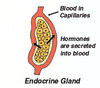

אנדוקרינית - החומר שמיוצר בבלוטה מופרש לממברנה הבזאלית. ההפרשה היא ל”סביבה הקרובה”.

בלוטה אנדוקרינית - סיווג

cord and clump- ההפרשה מרוכזת בתאים עצמם

follicle- ריקון של התאים למאגר מרכזי בעזרת זקיקים.